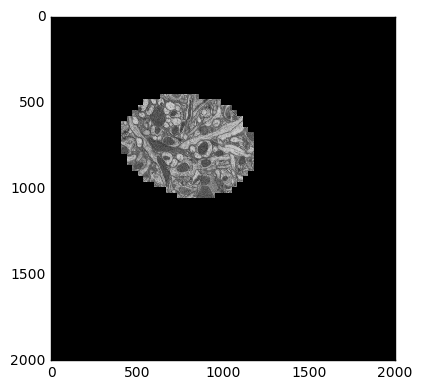

plt.figure(figsize=(8, 8))

skimage.io.imshow(recenter(sample))

Recentered image

Now we map this function across our distributed array.

We check our work by averaging our re-centered images across time and displaying that to the screen. We see that our images are better centered with each other as expected.

skimage.io.imshow(recentered.mean(axis=0))

Recentered time average